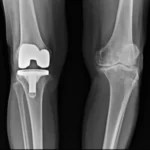

Curado de una infección por estafilococo en una prótesis de rodilla mediante fagoterapia.

Cuando volví a ver a mi cirujano hace dos meses para decirle que por el momento no quería ser operado nuevamente, me confirmó, basándose en mis buenos análisis y radiografías, que no era necesario; lo veríamos en 6 meses. Pero no me hizo ninguna pregunta sobre los fagos… Me sirvió no haberles escuchado y haber optado por la mencionada fagoterapia. ¡Gracias, Georgia! ¡Gracias, fagos! ¡Gracias, atención médica en Georgia!